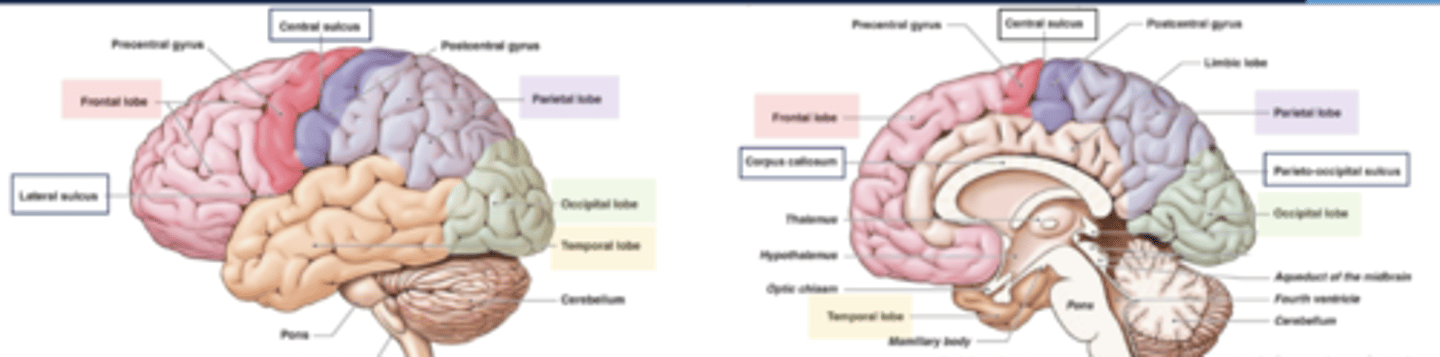

list the functions of the frontal lobe:

1. movement

2. executive functions

3. problem solving

4. reasoning/judgement

5. behaviors (emotions)

6. language production

7. memory

list the functions of the parietal lobe:

1. sensation

2. body orientation

3. spatial relationships

~primary somatosensory cortex~

list the functions of the temporal lobe:

1. language comprehension

2. hearing

3. behavior

4. memory

list the functions of the occipital lobe:

1. vision

2. color perception

list the functions of the cerebellum:

1. balance

2. coordination

3. fine muscle control

list the functions of the brainstem:

1. breathing

2. blood pressure

3. heartbeat

4. swallowing

5. alertness/sleep

6. body temperature

7. digestion

what are the boundaries of the frontal lobe?

central sulcus and lateral fissue

what are the boundaries of the parietal lobe?

central sulcus, lateral fissure, parieto-occipital sulcus

what are the boundaries of the occipital lobe?

parietal-occipital sulcus

what are the boundaries of the temporal lobe?

lateral fissure